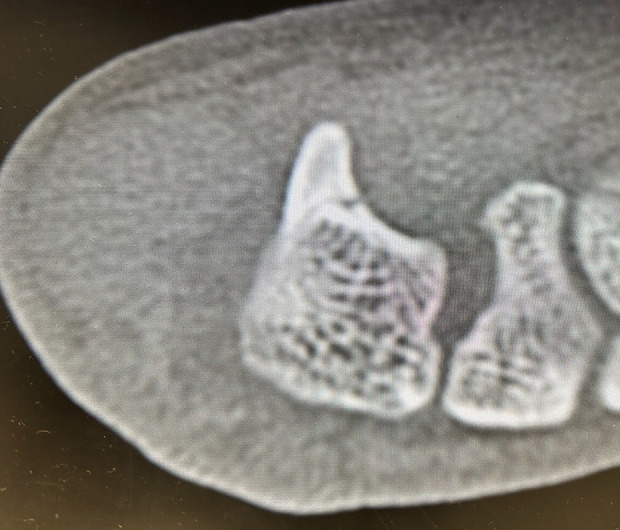

BACKGROUND Early diagnosing a stress fracture of the hook of the hamate is challenging with plain X-rays alone. However, it is necessary to determine the appropriate treatment method to allow athletes to return to sports as soon as possible. We present a case in which diagnosis of stress fracture of the hook of the hamate in a professional baseball player was confirmed on the day of injury by ultrasound imaging, and early intervention was performed. CASE REPORT The patient was a 22-year-old male professional baseball player. During hitting practice, he experienced pain in his right palm, then tenderness around the hook of the hamate was noted. Ultrasonography revealed disruption of the bony cortical continuity of the ulnar aspect of the hook of the hamate and a hematoma around this lesion. Stress fracture of the hook of the hamate was confirmed by computed tomography. Resection of the hook of the hamate was performed on the third day after injury. The patient returned to playing baseball 3 months after surgery. CONCLUSIONS In stress fracture of the hook of the hamate, the time required for diagnosis greatly affects the time to return to competition. To solve this clinical issue, ultrasonography was applied to the early diagnosis of stress fractures of the hook of the hamate. This study suggests that ultrasound can be a useful diagnostic tool for early diagnosis of stress fractures of the hook of the hamate.